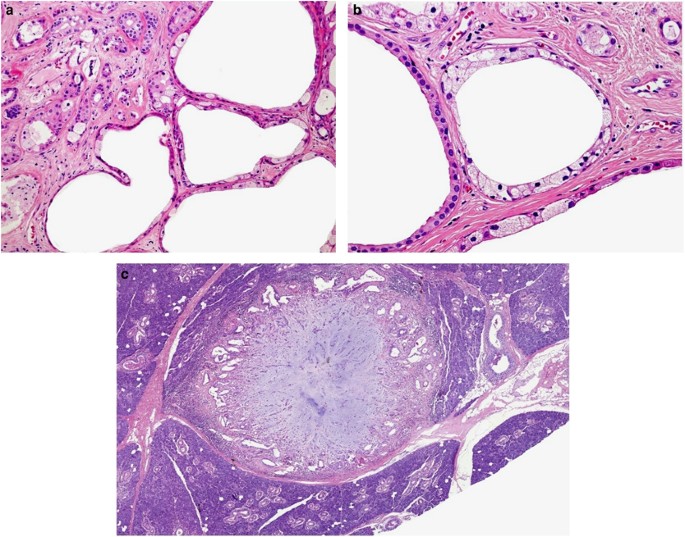

SPAs are well-circumscribed tumors with multiple, densely sclerotic, irregularly defined lobules composed of abundant hyalinized collagen surrounding variably sized collections of ducts with varying degrees of cystic change (Figure 4a). The lesions are frequently unencapsulated, but may have a more or less complete pseudocapsule. The key histological features of SPA include lobular proliferation of ductal and acinar cells, the latter often containing large eosinophilic cytoplasmic zymogen-like granules (PAS-positive, diastase resistant). Not uncommonly, these granules may reach such a size so as to appear as intracytoplasmic globules (Figure 4b). The ductal cells show variable cytomorphological characteristics, including foamy, vacuolated, apocrine, mucous, clear, squamous, columnar and oncocyte-like cells (Figures 4c and d). In addition, the focal presence of true acini composed of distinctly serous cells, juxtaposed to the more commonly occurring and characteristic eosinophilic, granulated acinar cells can be occasionally observed. In most cases, a variably prominent, cystic component is present. The cysts may be lined by flattened, apocrine or vacuolated cells (Figure 5a). Partly, the epithelial cells lining the cysts may be denuded and replaced by foamy macrophages (Figure 5b). Most commonly, the cellular components in SPA are embedded in a sharply delineated, dense, sclerotic collagenous stroma. The stroma may on occasion form hyalinized hypocellular nodules/plaque-like structures that may or may not contain residual epithelial cellular remnants and/or vacuolated foam cell-type macrophages. In addition, the stroma may also display a distinctly myxoid or even myxochondroid quality (Figure 5c). Commonly, the stroma harbors a variably intense, frequently nodular chronic inflammatory infiltrate. The acinar component may or may not show preservation of the lobular architecture. In the latter case, a sclerosing adenosis-like histopathological pattern is encountered and when this is associated with a stroma-induced distortion of the acini/ductules, the process may acquire an infiltrative appearance. Moreover, as described in a few cases by Gnepp et al,59 stromal distortion may lead to the formation of radial scar-like structures. In addition, cases of SPA with dysplastic epithelial changes have been reported, and this may be severe enough to resemble low-grade ductal carcinoma in situ (DCIS) of the breast56, 57, 59, 67, 70 (Figures 6a and c).

Sclerosing polycystic adenoma (SPA). (a) SPAs are well-circumscribed tumors with multiple, densely sclerotic, irregularly defined lobules composed of abundant hyalinized collagen surrounding variably sized collections of ducts with varying degrees of cystic change. (b) The hallmark of SPA are acinar cells with coarse cytoplasmic eosinophilic granules. The ductal cells show variable cytomorphological characteristics, including foamy, vacuolated (c), apocrine, mucous, clear, squamous, columnar and oncocyte-like cells (d).

Sclerosing polycystic adenoma (SPA). (a-c) The cysts may be lined by flattened, apocrine or vacuolated cells (a). Partly, the epithelial cells lining the cysts may be denuded and replaced by foamy macrophages (b). In addition, the stroma may also display a distinctly myxoid or even myxochondroid quality (c).

Sclerosing polycystic adenoma (SPA). (a-c) The tumor is composed of proliferating solid and tubular ductal structures separated by abundant fibrous stroma (a). Area with mild to moderate dysplastic epithelial changes with cribriform growth pattern consistent with ductal carcinoma in situ (b). More cellular foci with solid and tubular growth pattern within hyalinized sclerotic stroma are seen (c).